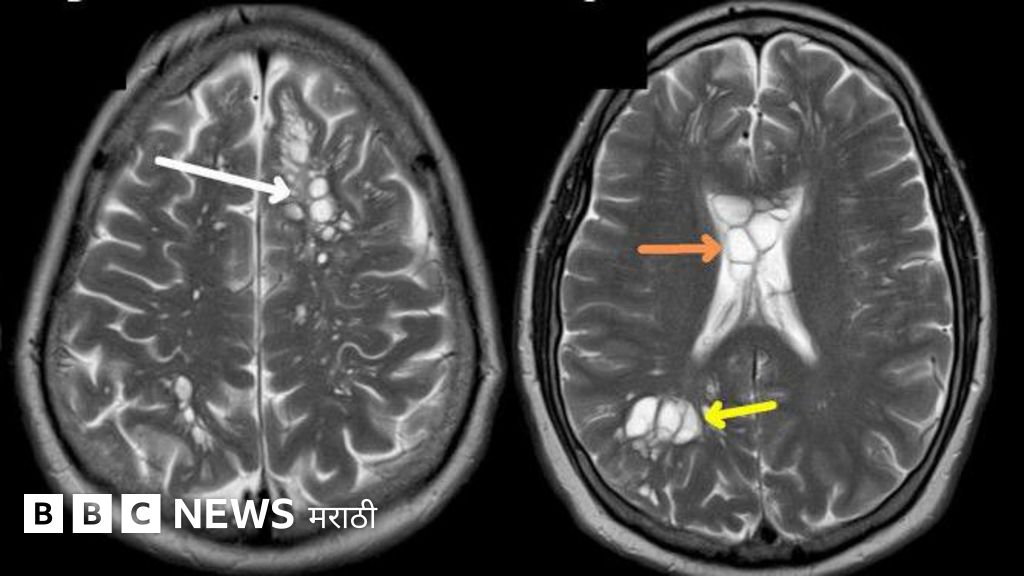

अमेरिकेत काही दिवसांपूर्वी एक व्यक्ती डॉक्टरांकडे आली होती. मला सतत मायग्रेनचा त्रास होतोय, असं त्यांनी सांगितलं. स्कॅन केल्यानंतर डॉक्टरांना त्यांच्या मेंदूत चक्क जंत आढळले.

लांबलचक जंत एका रिबिनसारखे गुंडाळलेल्या अवस्थतेत होते.

त्यानंतर डॉक्टरांनी स्कॅन केले आणि त्याच्या मेंदूमध्ये जंत आढळल्याची धक्कादायक माहिती समोर आली.

या जंतांमुळे पीडितेला सिस्टोसेरकोसिस आजार झाला होता.

सिस्टीरकोसिस (Cystocercosis) हा एक प्रकारचा संसर्ग आहे जो परजीवी Taenia solium (T.solium) च्या अळ्यांमुळे होतो. त्यांना डुकराचे टेपवर्म असंही म्हणतात. या घटनेनंतर मेंदूमध्ये सिस्ट्स म्हणजेच गाठी तयार होऊ शकतात.

मेंदूमध्ये अशा सिस्टच्या उपस्थितीला न्यूरोसिस्टोसेरकोसिस (Neurocystocercosis) म्हणतात.